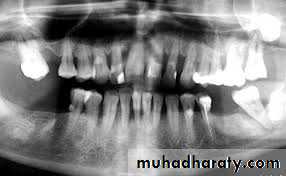

• Radiographs

• A complete series of periapical and bitewing radiographs is essential for complete examination.• Panoramic radiographs are ideal for screening for pathologic conditions.

• Excellent periapical radiographs are essential for determining the crown/ root ratio of the remaining teeth, the status of periodontal ligament space, and lamina dura, quality of ridge in the edentulous areas.